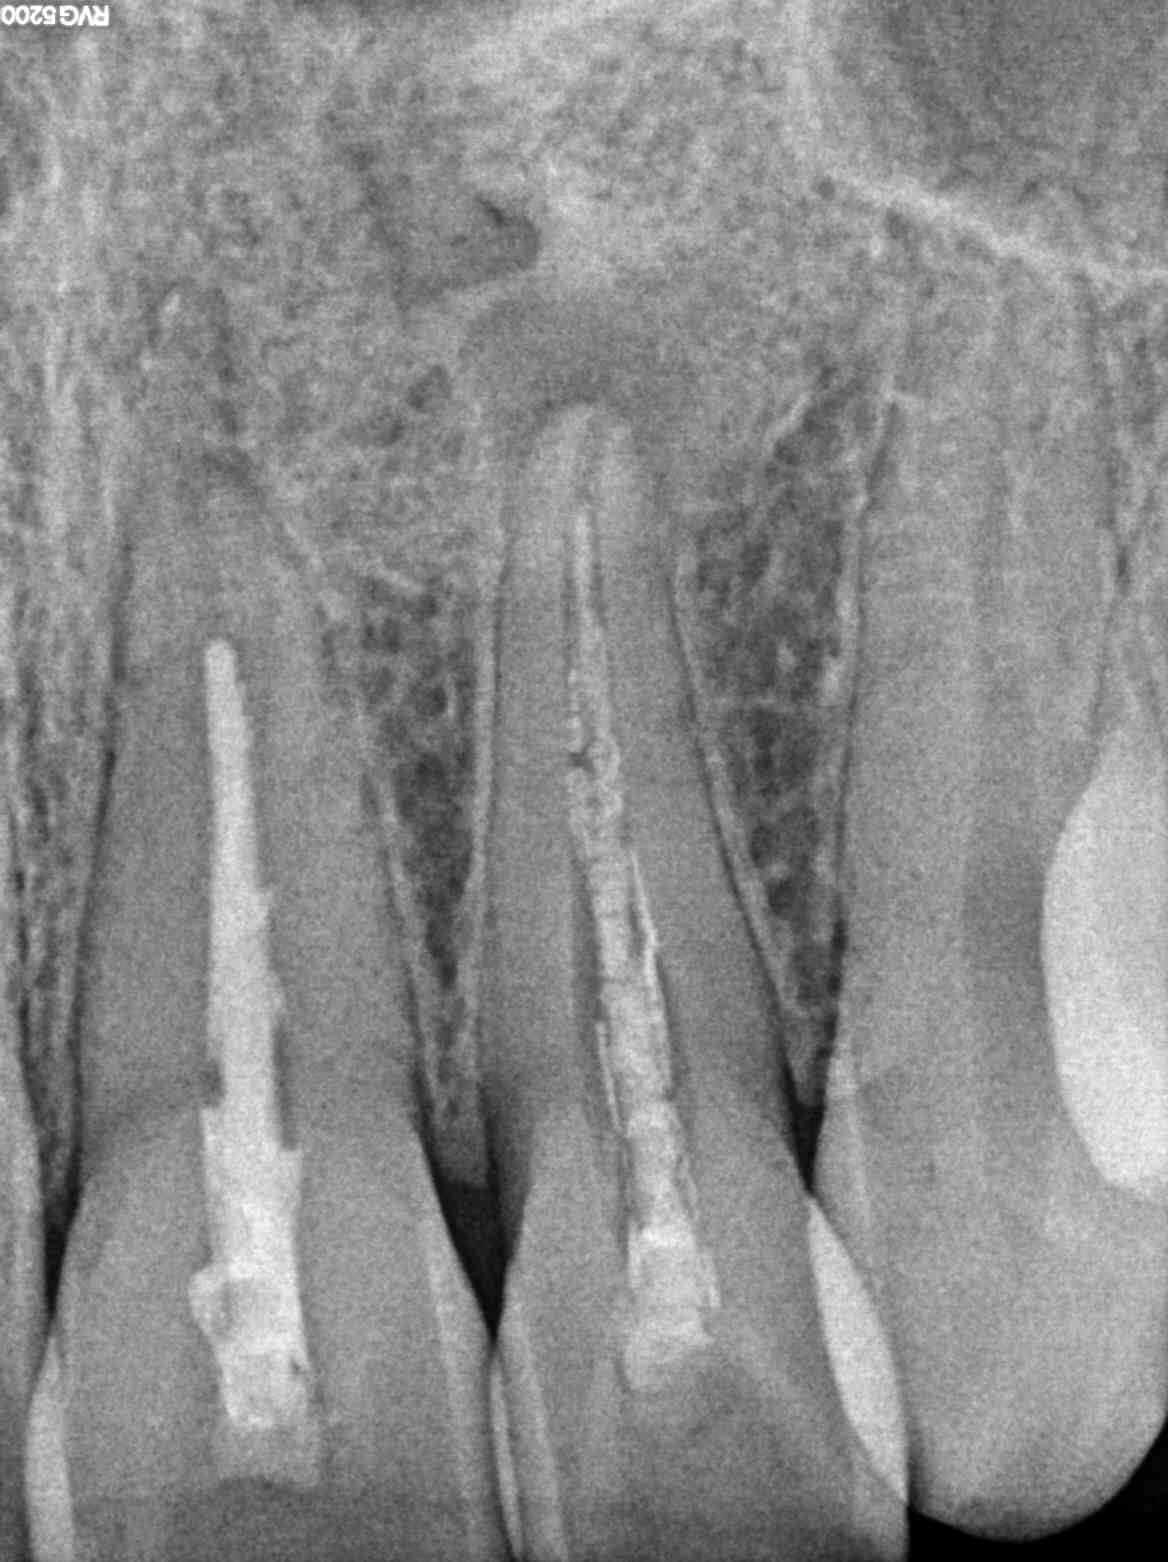

• توضع ملفات دواره صغيرة تقوم بإزالة النسيج الميت والمصاب.

• استخدام مواد التنظيف المطهرة لتنظيف وتطهير تلك القنوات.

•  وأخيرا يتم إضافة الحشو لسد التجاويف في الضرس، ولكن يجب أن يسد الطبيب التجاويف بالكامل حتى لا يدع مجال للبكتيريا أن تنمو.

نقوم باستخدام اجهزة قياس طول القنوات العصبيه الأدق على الإطلاق في العالم حتى لا يخرج حشو العصب أقصر أو أطول من المطلوب.

نستخدم اجهزة حقن حشو العصب السائل الذي يقوم بملأ كل قنوات العصب الرئيسيه والجانبيه بشكل محكم للغايه حتى لا نترك أي فراغات لنمو البكتيريا.

كل الخطوات تتم بإستخدام الميكروسكوب ذو القدره التكبيريه العاليه لضمان اقصى درجات الدقه وايضاً للفحص الدقيق عن أي قنوات فرعيه زائده قد تسبب فشل الحشو بعد ذلك.